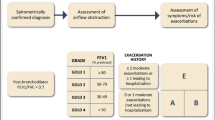

A diagram summarizing the diagnostic workup in patients with acute dyspnea is reported in Fig. 2.

Summary of the diagnostic workup in patients with acute dyspnea presenting at the emergency department. BNP: B type natriuretic peptide; NT-proBNP: N-terminal pro B-type natriuretic peptide; hs-cTn: high sensitivity cardiac troponin; CT: computed tomography; PaO2: arterial partial pressure of oxygen; PaCO2: arterial partial pressure of carbon dioxide; HCO3−: bicarbonate